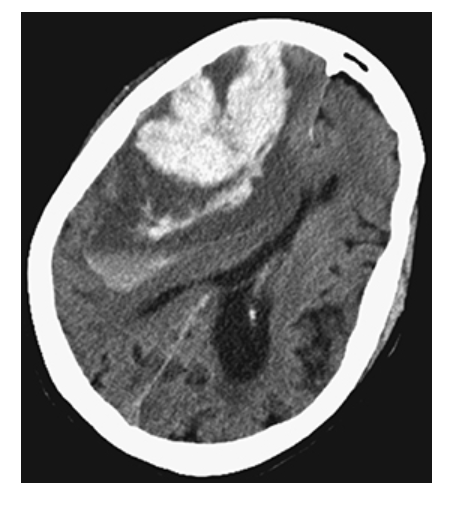

Intracerebral Hemorrhage. Axial NECT shows a large hyperdense region in the right parietal lobe consistent with acute hemorrhage. This is surrounded by low-attenuation cerebral edema. Note the mass effect and midline shift.